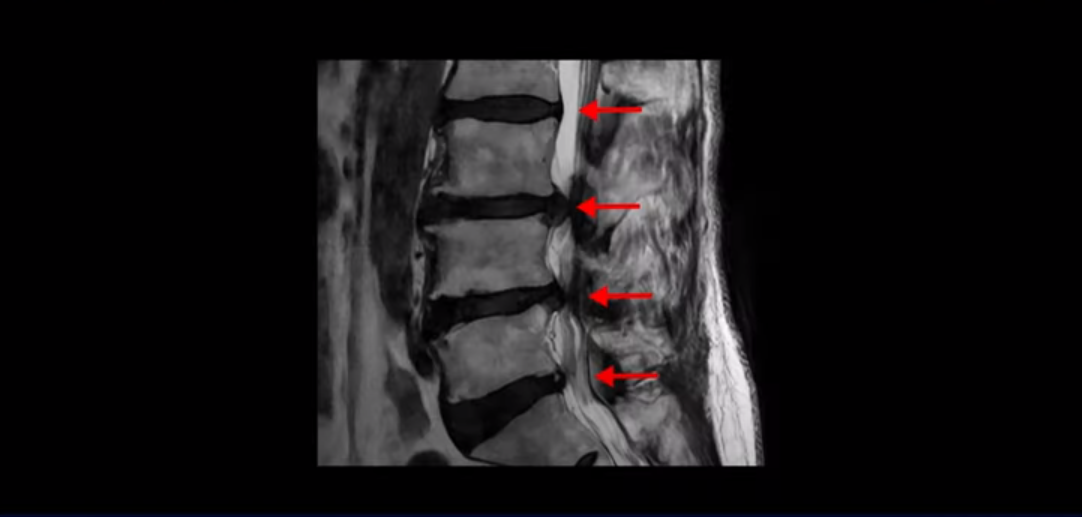

먼저 이분 MRI를 보면서 설명 드린 후 어떻게 이런 신경이 눌리는 환자분이 수술 없이 치료가 될 수 있는지, 왜 수술 없이도 협착증이 좋아질 수 있는지, 근육재활치료와 운동은 어떻게 하는 건지 자세히 설명 드리겠습니다.

이분은 허리부터 다리, 복숭아뼈까지 극심하게 저리고 아픈 분입니다. MRI를 보시면 허리 4마디가 안 좋습니다.

그중에서도 3번 4번과 4번 5번 마디가 가장 안 좋습니다. 보시다시피 두 마디에 심한 중심성 협착이 있습니다.

이렇게 허리에서 신경이 눌리니까 다리가 저리고 종아리가 터질 듯이 아픕니다. 그래서 걷지를 못하고 가다 쉬고 가다 쉬고 그런 겁니다. 그런데 이런 분들이 수술 없이 치료가 가능한 이유는 근육재활치료와 운동으로 근육이 좋아지면 허리를 더 잘 지탱해 주니까 신경이 덜 눌리게 되는 겁니다. 모든 협착증 환자는 신경 구멍도 좁아져 있지만 근육도 다 망가져 있습니다.